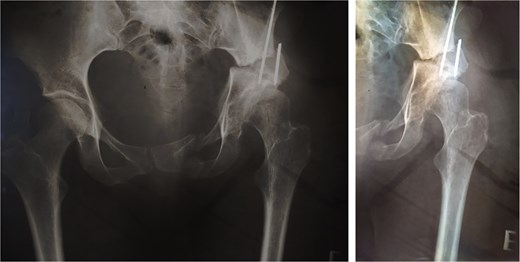

In 1984, a 35-year-old female patient presented to our department with severe left groin pain. Preoperative pelvic radiographs revealed acetabular dysplasia with subluxation at Crowe Grade I and Tönnis Grade I. A Pol Le Cœur corrective TPO was performed (Fig. 1). Over the following 28 years, radiographic examinations demonstrated progressive articular degradation despite the initial clinical success of the osteotomy.

Postoperative anteroposterior radiographs of the pelvis, showing Pol Le Cœeur triple pelvic osteotomy performed on a 35-year-old female patient to treat an acetabular dysplasia in the left hip, at Grade 1 Crowe’s classification.